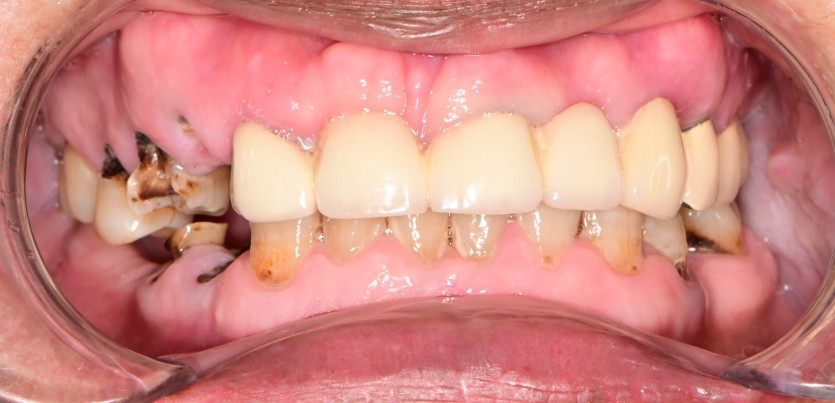

만 61세 상악 전체 임플란트 증례(하악 일부)

상악 전체 임플란트 증례입니다.(하악 일부)

15개의 임플란트로 완성하였습니다.